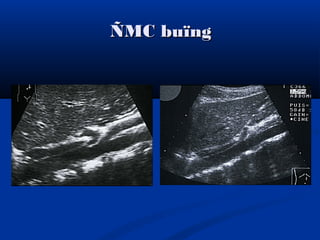

ÑMC buïngÑMC buïng

ÑMC buïng vaø TMC döôùiÑMC buïng vaø TMC döôùi